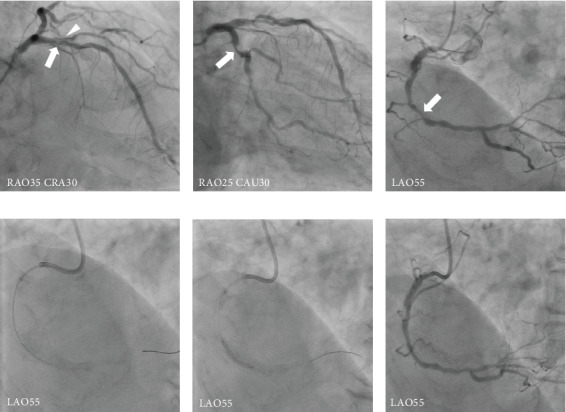

Patients on hemodialysis with concomitant severe aortic stenosis (AS) and multivessel coronary artery disease (CAD) are at high risk for surgical aortic valve replacement (SAVR) and coronary artery bypass grafting (CABG). Transsubclavian-transcatheter aortic valve implantation (TSc-TAVI) is a well-established alternative approach to transfemoral TAVI for patients with unfavorable femoral access. Herein, we report a case in which minimally invasive surgical treatment and TSc-TAVI were performed simultaneously in a patient with severe AS and multivessel CAD undergoing hemodialysis. An 85-year-old man undergoing hemodialysis for end-stage renal disease owing to severe AS (mean pressure gradient, 46 mmHg; aortic valve area, 0.75 cm2; and left ventricular ejection fraction, 59%) presented to our hospital with chest pain on exertion. Preoperative coronary angiography revealed significant stenosis of the left anterior descending (LAD) coronary artery and right coronary artery (RCA), requiring revascularization. However, the patient was not a good candidate for transfemoral TAVI because of a porcelain ascending aorta and a shaggy descending aorta observed on computed tomography. He was scheduled for concomitant right TSc-TAVI and minimally invasive cardiac surgery (MICS)-CABG after percutaneous coronary intervention (PCI) for the RCA. The treatment was successful. Simultaneous TSc-TAVI and MICS-CABG with PCI may be applied as a minimally invasive surgical treatment modality for patients with AS and CAD undergoing hemodialysis.